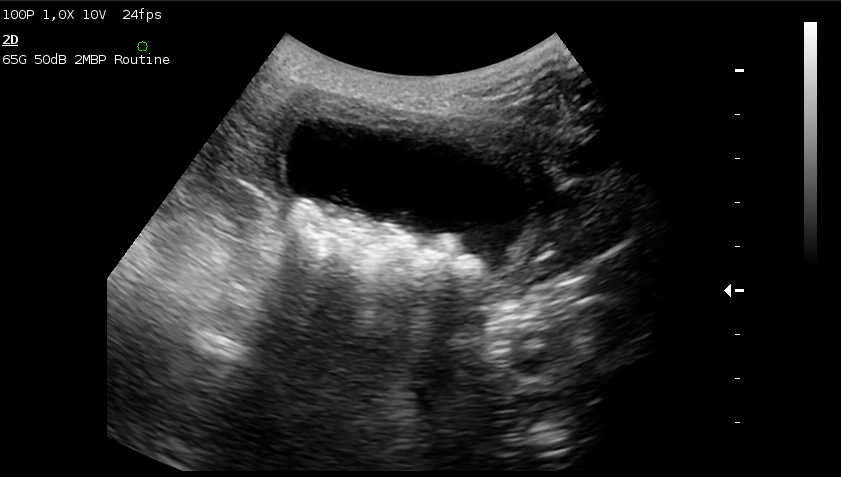

УЗИ: собака, 10 лет, уроцистолитиаз (камни в мочевой пузыре)

Каждая разновидность имеет типичную форму, что позволяет определить характер конкремента уже на стадии ультразвукового обследования. Существует множество частных случаев, но в основном это следующие химические группы: